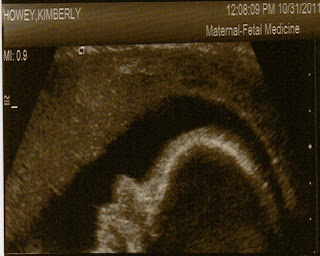

Latest profile pic of Cason